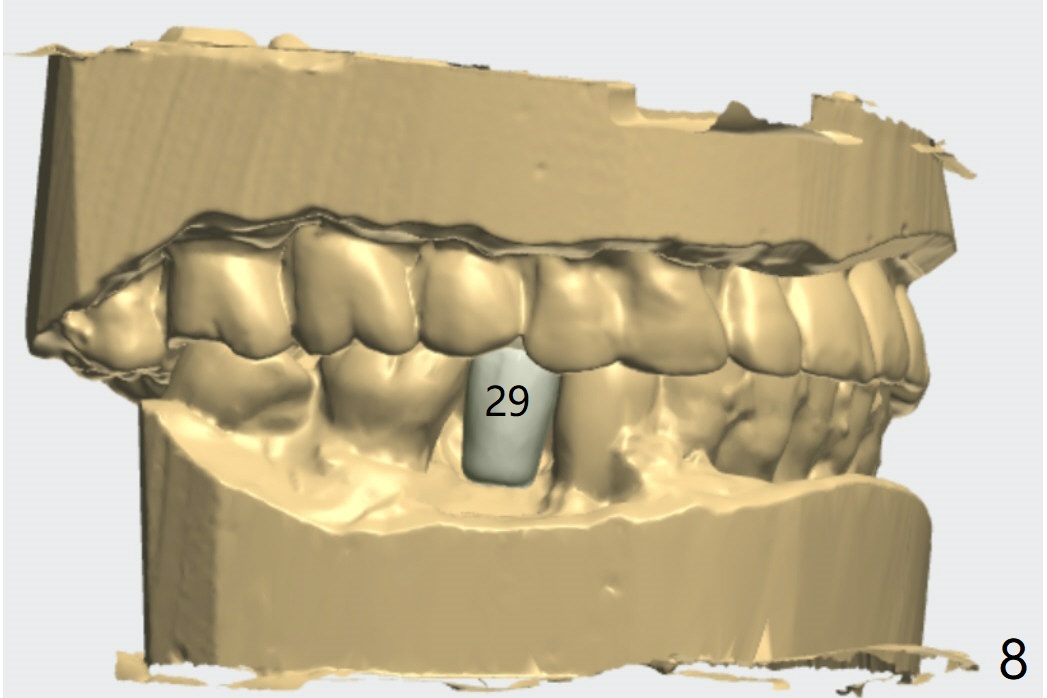

Return to Upper Molar Lower Premolar Immediate Implant, Trajectory